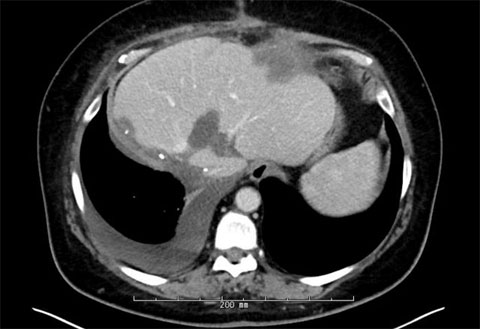

The patient responded well to chemotherapy; in a six-month period from December 2021 to May 2022, there was a significant interval decrease in the size of multiple hepatic metastatic lesions. The patient had approximately 22 peripherally enhancing liver metastases.

Pre-treatment MRIs